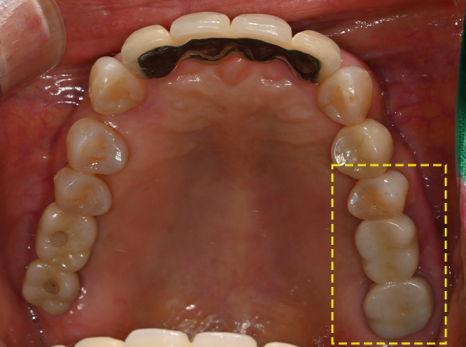

The photos above show the implant that was actually removed.

The screw body had snapped due to metal fatigue,

and around the head there was a large amount of tartar and inflammation.

The surrounding gum bone had melted away,

which eventually led to extraction of the adjacent tooth as well.